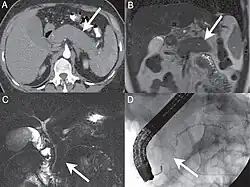

| A. Axial CT image in the pancreatic parenchymal phase shows the typical enlarged, poorly enhancing gland. B. Coronal T2 Weighted MR image demonstrates low signal intensity in the pancreas due to the diffuse fibrosis in the gland. C. Coronal MRCP image depicts a diffusely irregular pancreatic duct with stenosis distally in the pancreatic head. D. ERCP confirms the MR findings including the ductal stenosis. | |

Computed tomography (CT) findings in AIP include a diffusely enlarged hypodense pancreas or a focal mass that may be mistaken for a pancreatic malignancy.[8] A low-density, capsule-like rim on CT (possibly corresponding to an inflammatory process involving peripancreatic tissues) is thought to be an additional characteristic feature (thus the mnemonic: sausage-shaped). Magnetic resonance imaging (MRI) reveals a diffusely decreased signal intensity and delayed enhancement on dynamic scanning. The characteristic ERCP finding is segmental or diffuse irregular narrowing of the main pancreatic duct, usually accompanied by an extrinsic-appearing stricture of the distal bile duct. Changes in the extrapancreatic bile duct similar to those of primary sclerosing cholangitis (PSC) have been reported.